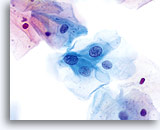

En raison de leur morphologie, les cellules issues de lésions de bas grade comptent parmi les anomalies intra-épithéliales les plus faciles à localiser et à identifier. En comparaison, les noyaux LSIL sont les plus grands et présentent un rapport N/C inférieur aux HSIL ou carcinomes. Ces cellules affichent une atypie nucléaire plus importante que les ASCUS (ce qui se traduit par une augmentation de la taille nucléaire, une irrégularité de la chromatine et une irrégularité de l’enveloppe nucléaire). Les noyaux peuvent occasionnellement ne pas être aussi hyperchromatiques que sur les frottis conventionnels, mais ils le sont toujours par rapport aux cellules normales environnantes. Les changements associés au HPV (par exemple, formation de cavités dans le cytoplasme) sont plus évidents grâce à la fixation liquide et à la technique de transfert, ce qui élimine la déformation des cellules associée à la méthode d’étalement conventionnelle. La méthode ThinPrep préserve mieux ces changements cellulaires, ce qui permet une meilleure distinction entre les véritables cavités cytoplasmiques induites par le HPV et les vacuoles bénignes/dégénératives et/ou les cellules malpighiennes glycogénées.

Comme il s’agit de cellules malpighiennes matures, elles gardent leur forme polygonale et conservent en partie leur taille normale. La taille des noyaux est au moins 3 à 4 fois supérieure à celle d’une cellule intermédiaire normale. En revanche, quand les changements associés au HPV sont évidents, les cellules peuvent être plus petites (quasiment parakératosiques), tout comme les noyaux (quelque peu pycnotiques) qui présentent en outre une binucléation et/ou multinucléation. Ces noyaux pycnotiques affichent en outre des caractéristiques anormales : hyperchromasie, augmentation de la taille par rapport à une cellule malpighienne superficielle normale, légère variation de la forme et de la taille, etc. Il est important d’insister sur le fait qu’une interprétation de LSIL/HPV implique des cavités cytoplasmiques nettes accompagnées de la morphologie nucléaire anormale décrite ci-dessus.